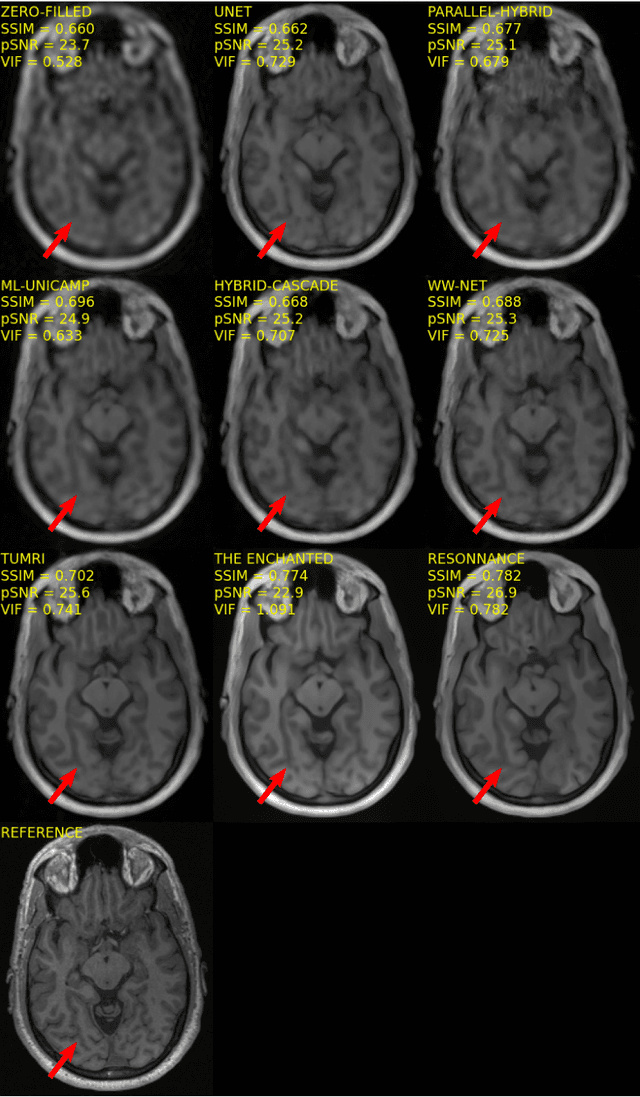

Abstract:The 2020 Multi-channel Magnetic Resonance Reconstruction (MC-MRRec) Challenge had two primary goals: 1) compare different MR image reconstruction models on a large dataset and 2) assess the generalizability of these models to datasets acquired with a different number of receiver coils (i.e., multiple channels). The challenge had two tracks: Track 01 focused on assessing models trained and tested with 12-channel data. Track 02 focused on assessing models trained with 12-channel data and tested on both 12-channel and 32-channel data. While the challenge is ongoing, here we describe the first edition of the challenge and summarise submissions received prior to 5 September 2020. Track 01 had five baseline models and received four independent submissions. Track 02 had two baseline models and received two independent submissions. This manuscript provides relevant comparative information on the current state-of-the-art of MR reconstruction and highlights the challenges of obtaining generalizable models that are required prior to clinical adoption. Both challenge tracks remain open and will provide an objective performance assessment for future submissions. Subsequent editions of the challenge are proposed to investigate new concepts and strategies, such as the integration of potentially available longitudinal information during the MR reconstruction process. An outline of the proposed second edition of the challenge is presented in this manuscript.